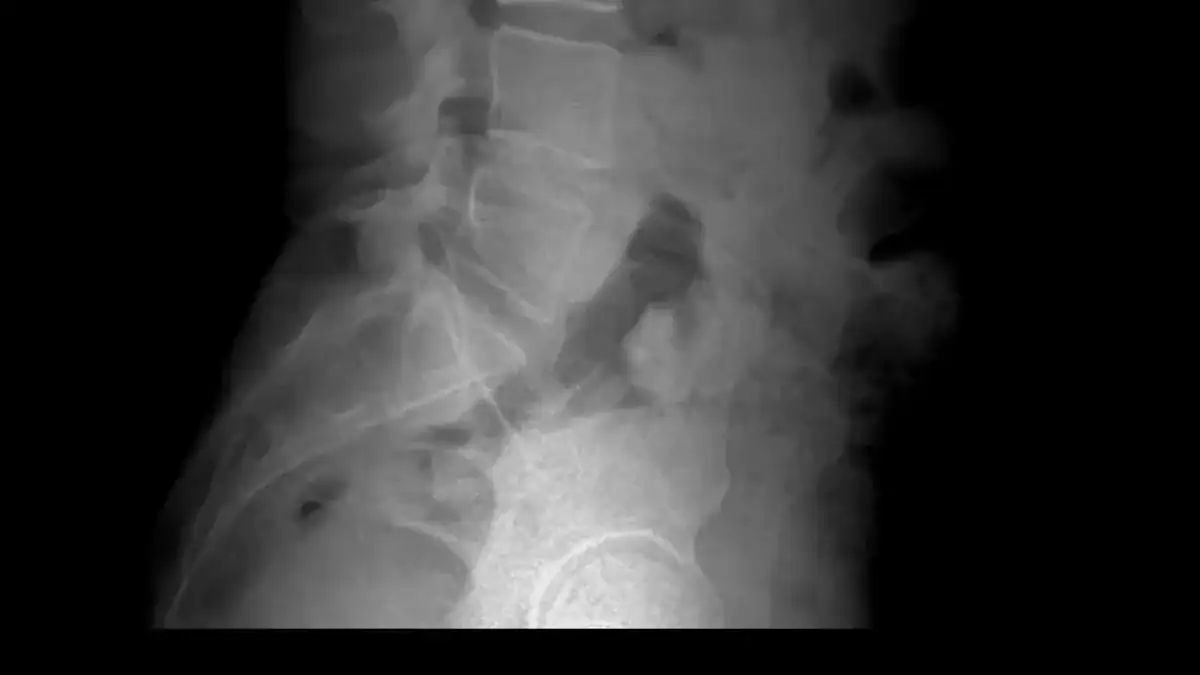

Diagnosing Radiculopathy and Nerve Compression

A herniated disc in the lumbar spine can press on nerve roots. This compression affects sensation in corresponding lumbar dermatomes. A dermatome is an area of skin. Sensory nerves from a single spinal nerve root supply this area. Dermatome maps show how spinal nerves innervate the skin. Sensory symptoms in a specific dermatome help locate suspected radiculopathy.